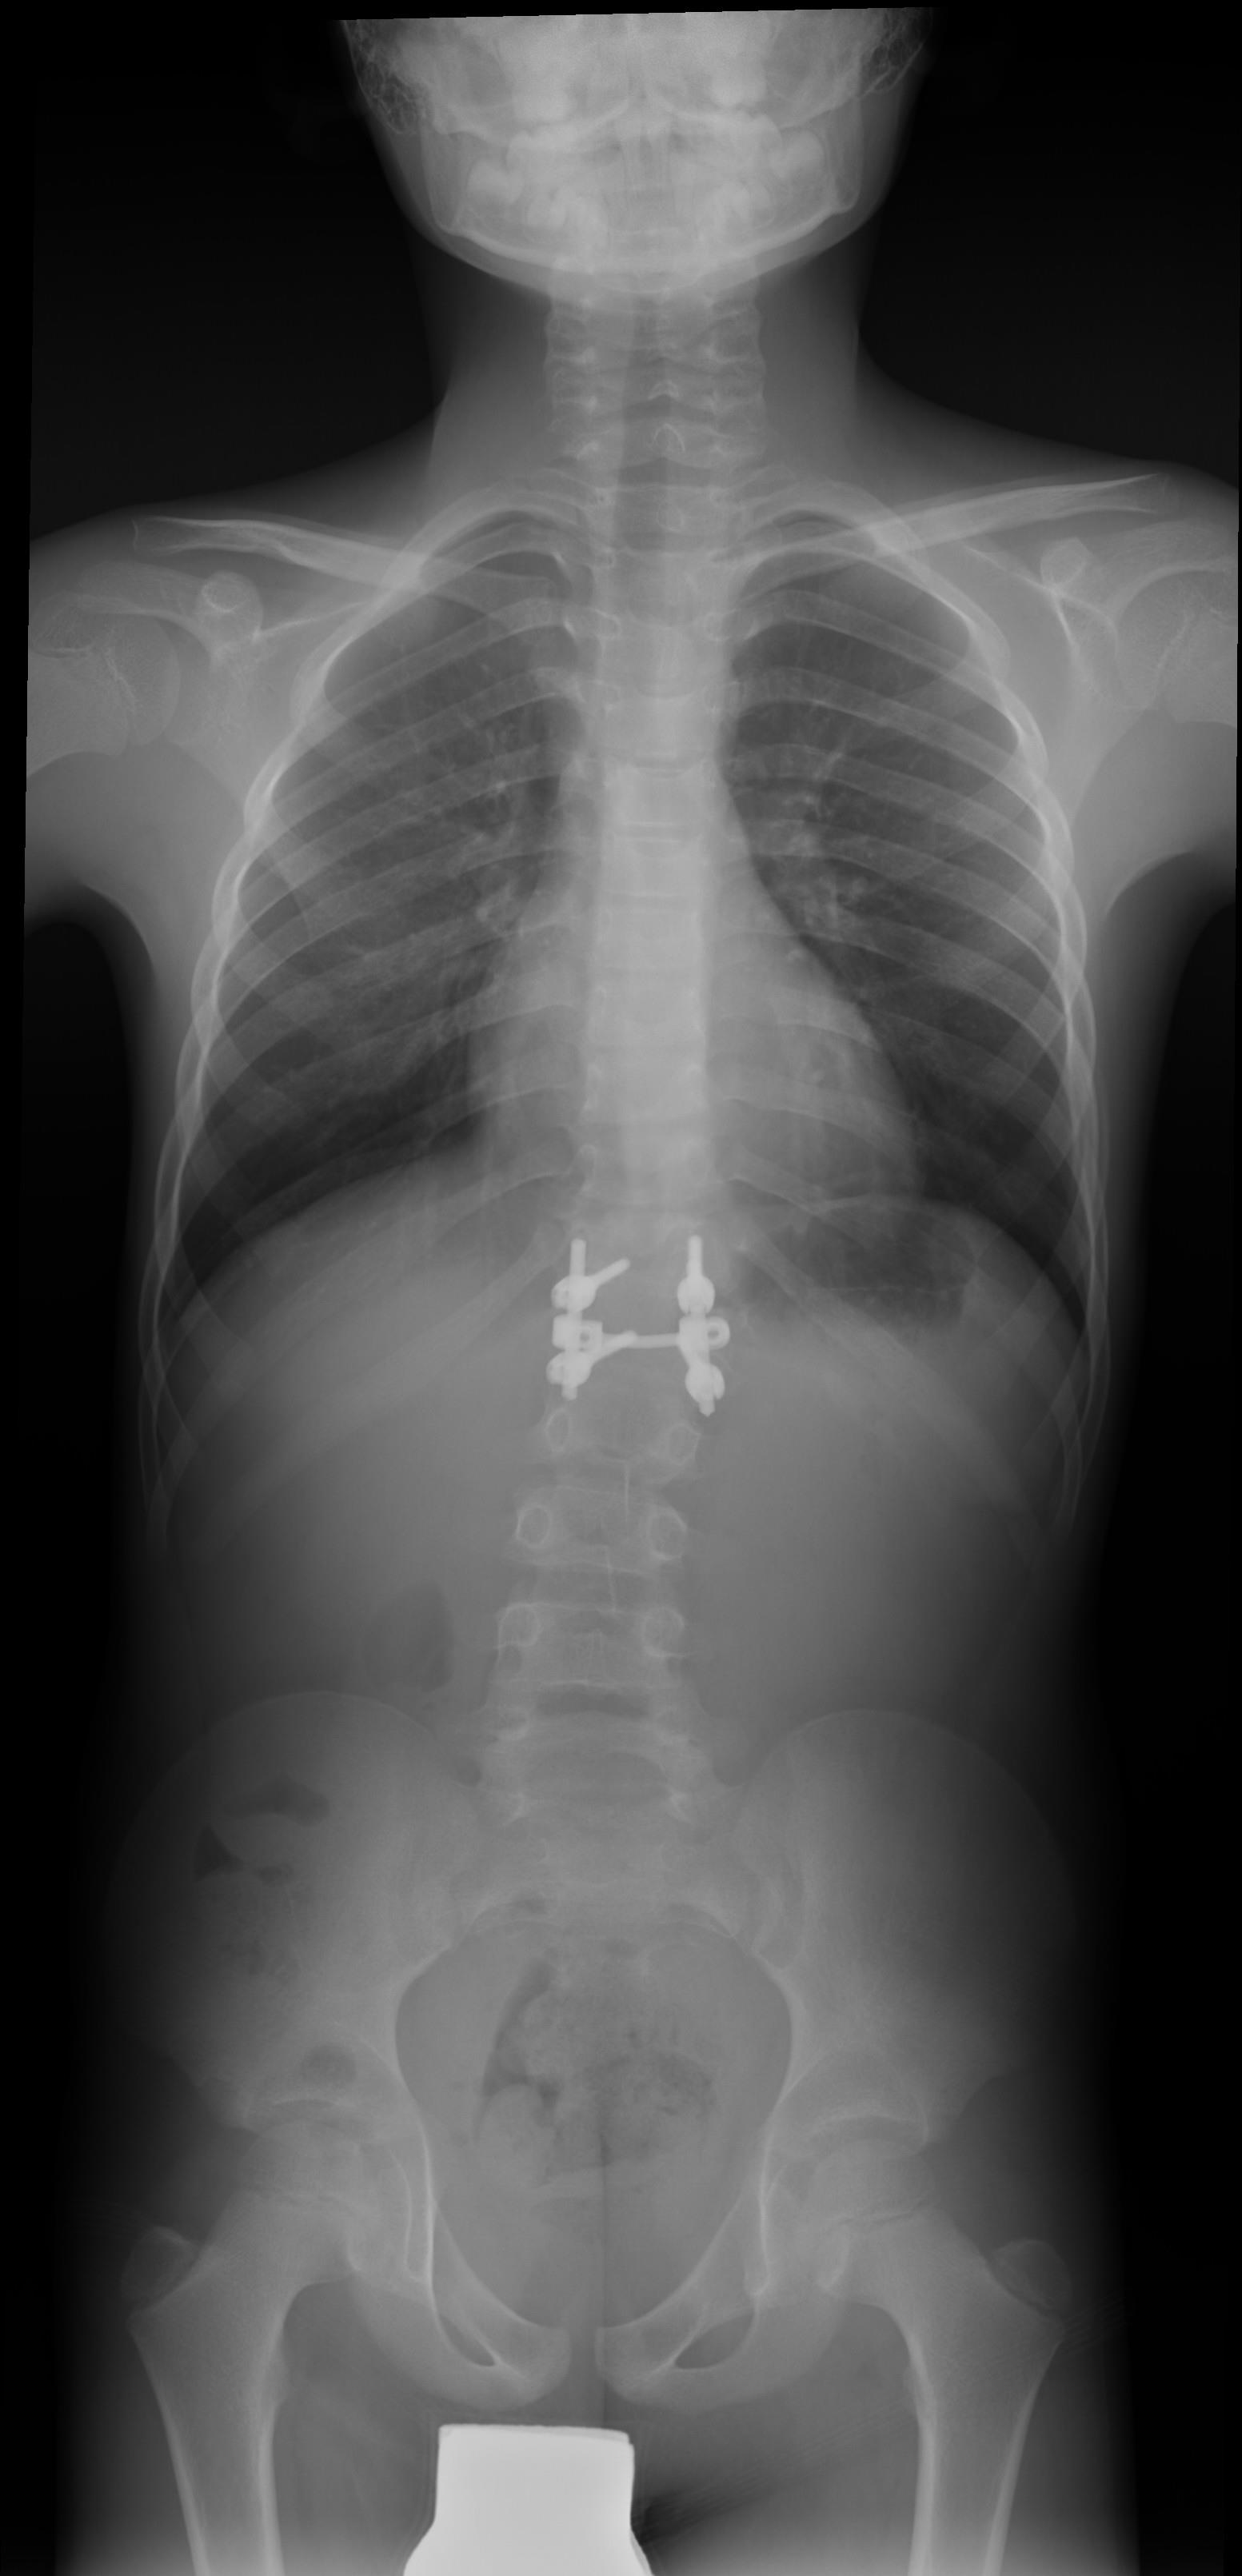

Telerradiografía de columna del mismo paciente 8 años postoperatoria, tras resección de hemivértebra y fusión T11-L1 (Fig 2)